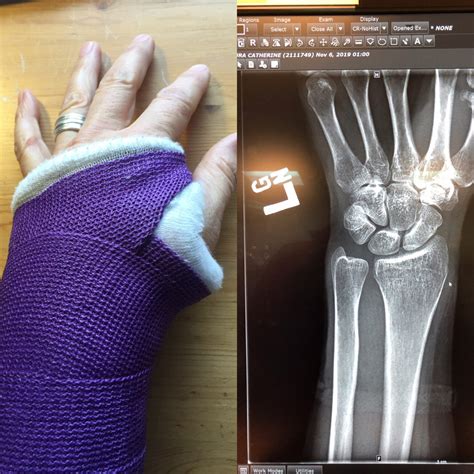

I Think I Broke My Wrist Is The First Thought After Falling

Broke my wrist after my skateboard turned off without warning at 25mph ...